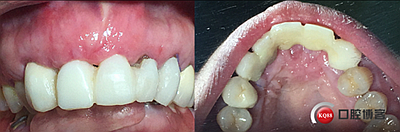

鄰牙重新備牙,制作臨時樹脂橋體,缺牙區(qū)三顆變?yōu)閮深w。下圖是術(shù)后一個月口內(nèi)照。

術(shù)后兩個月。

術(shù)后4個月,三顆牙變?yōu)閮深w牙齦乳頭改造是難點。

大家看看前后對比,效果不錯。